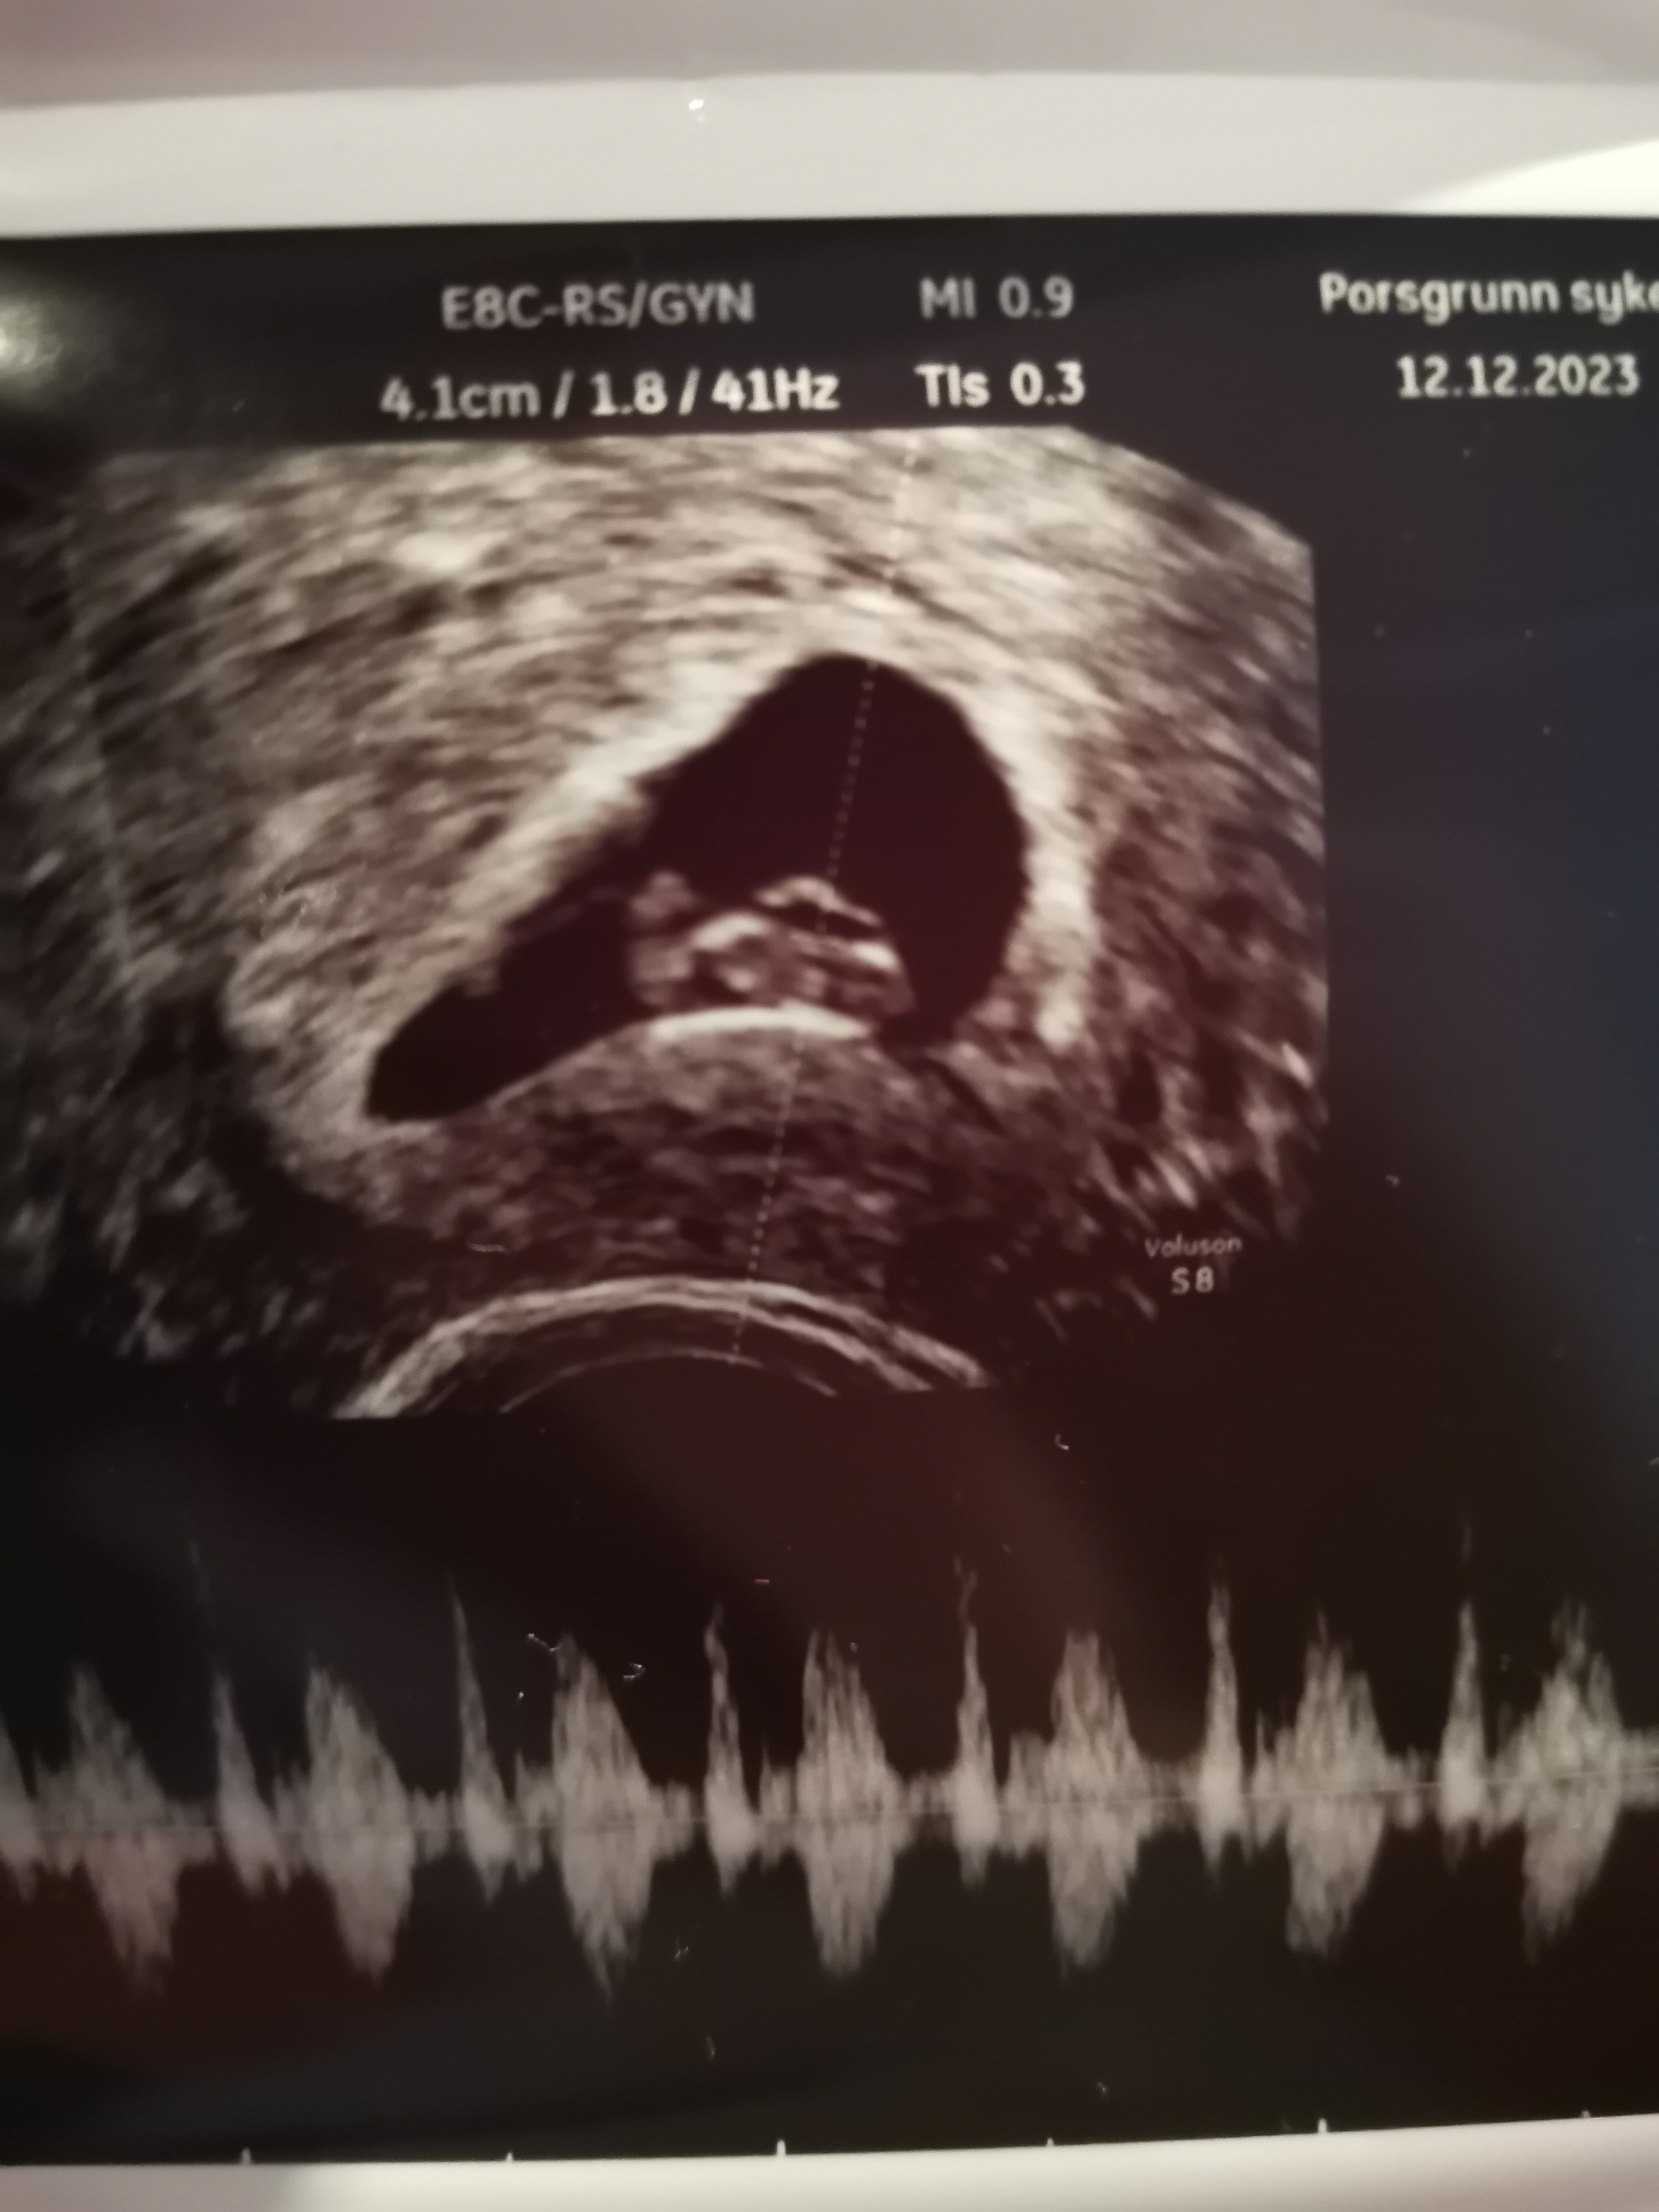

"Den første blodprøven er på 22000 og helt normal, slik den skal være hos en normal graviditet."

Uææ. Syns det er skummelt å kanskje tenke positivt! Kjenner liksom ingenting nedi der, ikke noe "jobbing".